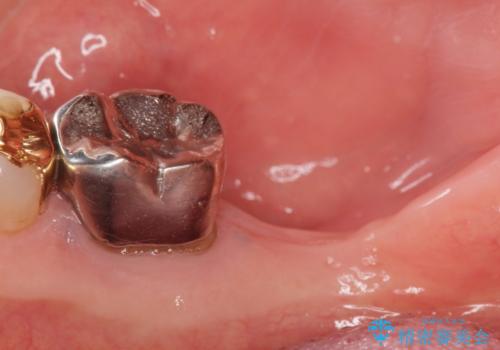

- 奥歯のインプラントをご希望し来院された患者様です。

骨が少なく下顎神経に近いことから、他院でインプラントできないと言われたとのことでした。

骨増生(GBR)を行い骨を増やすことでインプラント治療を可能にしました。

インプラントの種類:スプライン ツイスト (HAコーティング)

固定様式:セメント固定